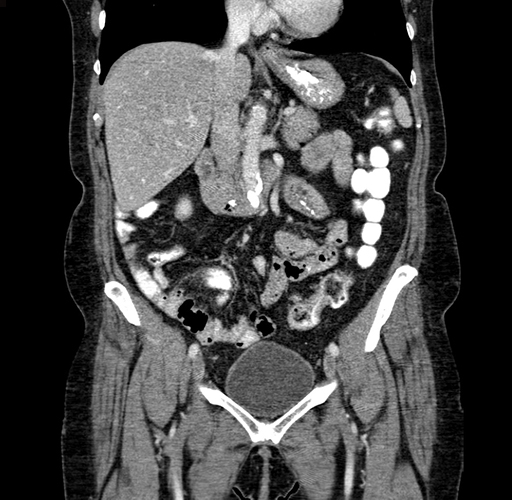

Pre-Chemo: Coronal Venous